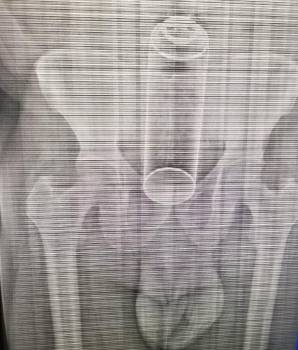

SANTO DOMINGO. El director del Servicio Nacional de Salud (SNS) informó que es un médico residente de anestesiología uno de los responsables de difundir, a través de las redes sociales, la imagen de una radiografía realizada a un paciente que fue intervenido quirúrgicamente en el hospital Francisco Moscoso Puello.

De igual manera, confirmó la veracidad de la imagen de un ambientador en un quirófano que también circula en los medios de comunicación y precisó que por ambas fotografías aún se investigan otros posibles responsables.

El señor de 40 años de edad, que llegó trasladado al referido hospital con un frasco de metal alojado en el tracto intestinal, se encuentra estable y fueron tomadas las medidas internas necesarias para preservar su identidad.